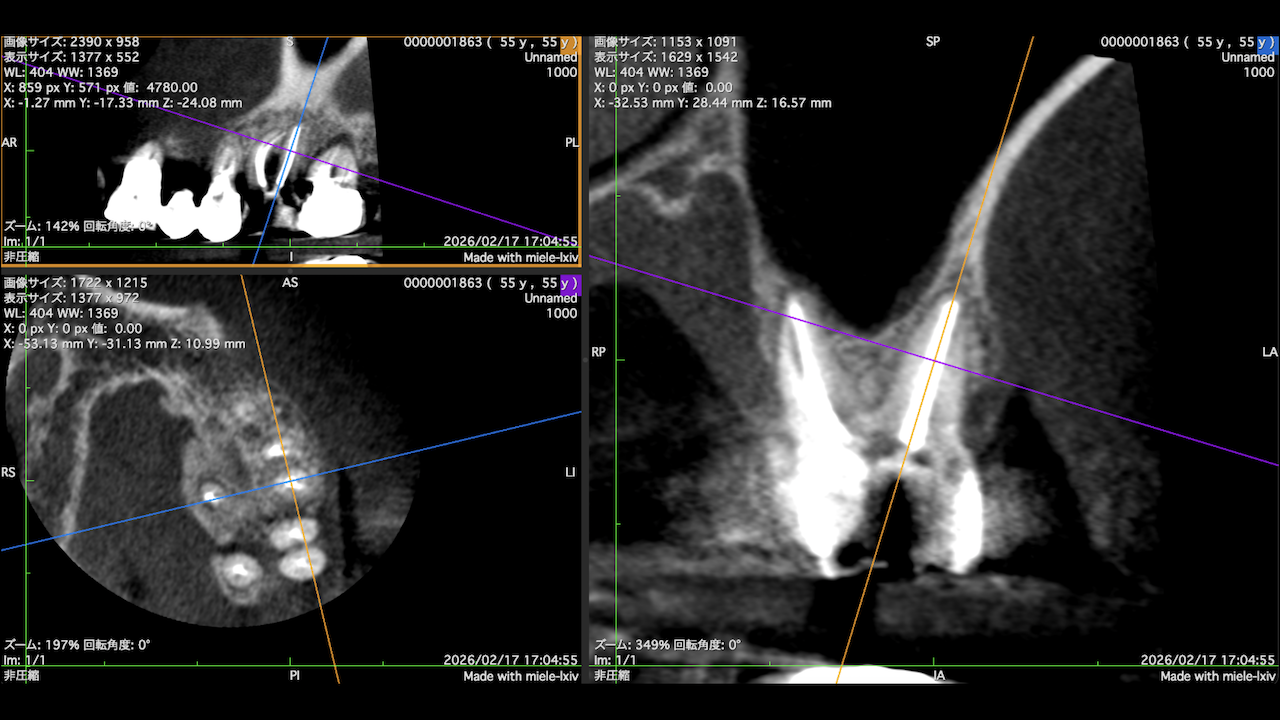

もう1ケースが以下だ。

#7がCold testに無反応である。

故に、#7,8の非外科的根管治療を行うことになった。

が、#8のメタルコアは外しにくいだろう。

CBCTでは2本とも口蓋側の皮質骨が消失している。

という絶望的な状況である。

ここから4ヶ月が経過すると…

臨床症状も皮質骨も大きく治癒している。

1年後の予後が気になるところであるが、すごくよくマネージメントできているだろう。